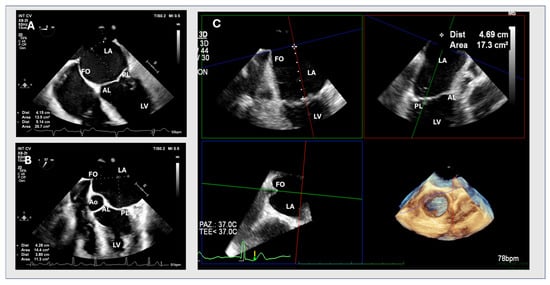

2.1. Two-Dimensional Method

2.2. MPR Method